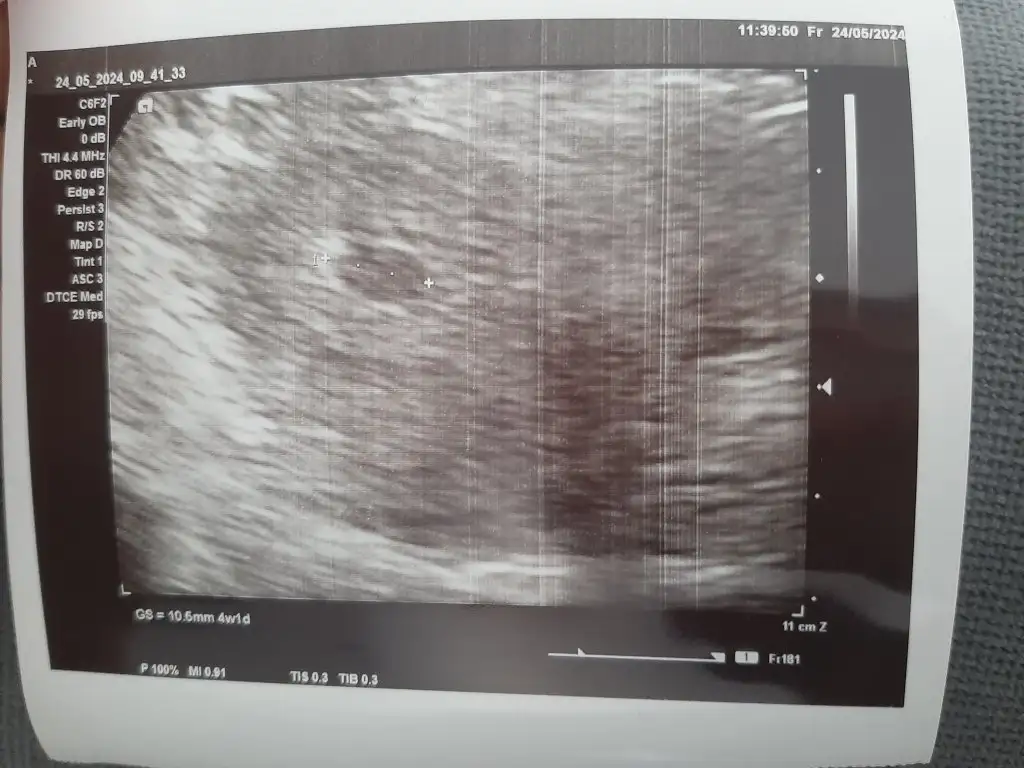

Doktor her şey yolunda kesenin yeri çok iyi dedi. Normalde 6+1 ama 4+1 göründü merak etme 2 hafta sonra net yaşını hesaplarız dedi. Ve Folic asit başladı. 😇🥰 Herkese sağlıklı gebelik dönemi diliyorum...

Kese: 4+1

Kalp atışı: 2 hafta sonra